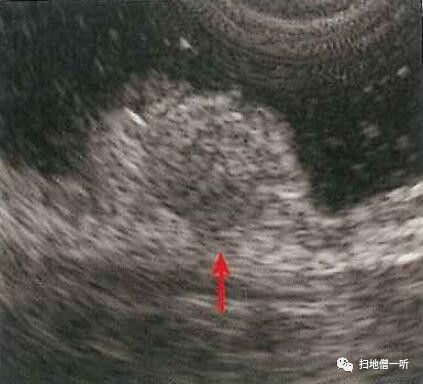

EUS可见粘膜内存在低回声团块,向下压向粘膜下层突起,可疑SM浸润